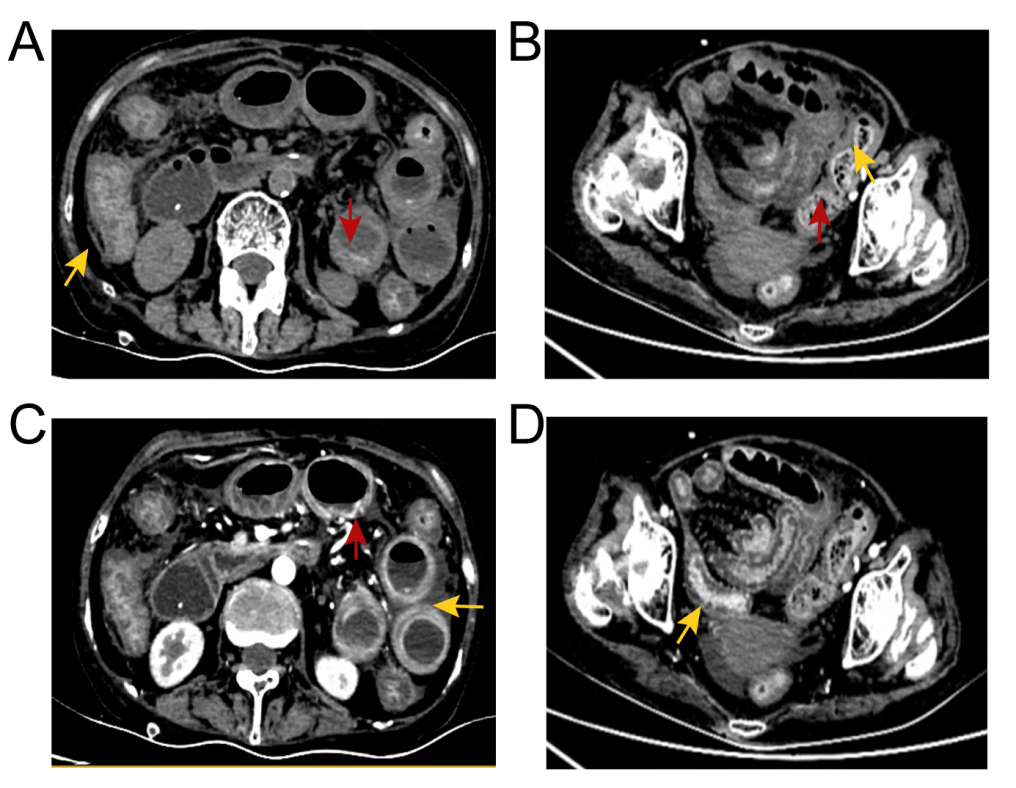

¸¹²¿ÅÌËã»ú¶Ï²ãɨÃèµÄ´ú±íÐÔͼÏñ¡£¡£¡£¡£¡£¡£»£»£»£»£»£»ÆÉ«¼ýÍ·ÏÔʾ³¦±ÚÔöºñºÍճĤˮÖ×£»£»£»£»£»£»ºìÉ«¼ýÍ·ÏÔʾð¤Ä¤³äѪ£»£»£»£»£»£»³¦±ÚÖÜΧģºýµÄÖ¬·¾¼ä϶Åú×¢¸¹Ç»»ýÒº¡£¡£¡£¡£¡£¡£

¸¹²¿ÅÌËã»ú¶Ï²ãɨÃè(CT)ÏÔʾ¸ÎÔà¡¢µ¨ÄÒ¡¢ÉöÔà¡¢ÒÈÏÙ¡¢×Ó¹¬ºÍ°òë×δ¼ûÒìÑù£¬£¬£¬£¬£¬µ«³¦±ÚÔöºñ£¬£¬£¬£¬£¬³¦±ÚÖÜΧ֬·¾¿Õ¼äÄ£ºý£¬£¬£¬£¬£¬Õ³Ä¤Ë®Ö×£¬£¬£¬£¬£¬¸¹Ç»ÖдæÓдó×Ú¸¹Ë®¡£¡£¡£¡£¡£¡£ÓÚÊÇ£¬£¬£¬£¬£¬ÔÚ³¬ÉùÖ¸µ¼Ï¶Ի¼ÕßÐи¹Ç»´©´ÌºÍ¸¹Ë®ÒýÁ÷¡£¡£¡£¡£¡£¡£¸¹Ë®Ñù±¾µÄ¿¹ËáȾɫ¡¢Î¢ÉúÎï×÷Óý£¨Ï¸¾úºÍÕæ¾ú£©¼°Ï¸°û²¡ÀíѧЧ¹û¾ùΪÒõÐÔ¡£¡£¡£¡£¡£¡£